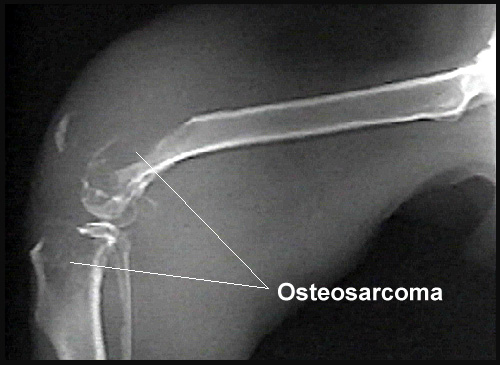

Фото 2. Скрининговое радиографическое исследование у собаки с фото 1. Выше коленки отмечены изменения характерные для остеосаркомы с классической локализацией поражения.

Общие отклонения на снимках при остеосаркоме заключаются в почти полном лизисе кости в зоне поражения совместно с остеобластическими и остеокластическими изменениями различной степени выраженности на периферии. Радиографическими особенностями остеосаркомы кости являются выраженный лизис кортикального слоя (вплоть до патологических переломов), формирование новой кости вокруг опухоли (типа вспышки солнца) с приподнятием надкостницы и значительное увеличение объема окружающих мягких тканей. На ранних этапах развития опухоли, радиографические изменения могут заключаться в потере ясного трабекуллярного паттерна метафиза и размытии переходной зоны в месте локализации опухоли. Радиографические изменения остеосаркомы собак зависят от размера, гистологического подтипа, локализации и времени развития опухоли. Радиографические признаки остеосаркомы сходны с таковыми при остеомиелите, особенно грибковом. Радиографические изменения при остеосаркоме кошек сходны с таковыми при остеосаркоме собак.

При рентгенографическом исследовании можно увидеть патологический перелом, лизис кости, и другие признаки, по которым уже можно поставить предварительный диагноз.